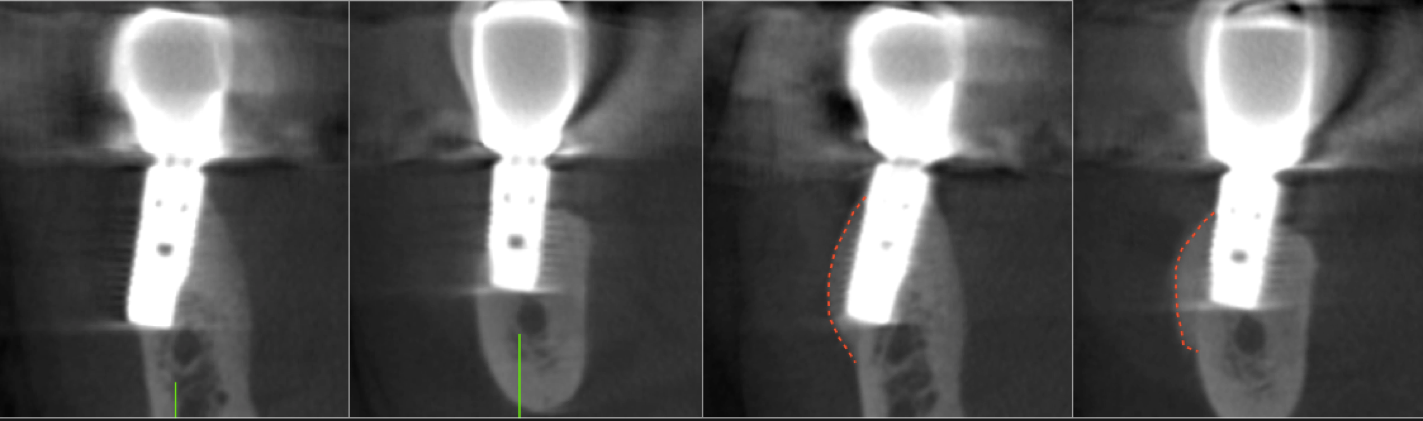

TREATMENT OF EXPOSED IMPLANT SURFACES

Bone regeneration over exposed implant surfaces is a novel application of the S.M.A.R.T. technique. Bone may be absent for a variety of reasons, usually related to placement or bone remodeling.

bone-grafting-dr-lee.png

As bone loss advances, implants may need to be removed and treatment started all over again. Traditional techniques have shown limited success in regenerating bone over implants. The S.M.A.R.T. technique has been successful in treating exposed implant surfaces with up to 3 year follow up. It provides a simplified, predictable and cost-effective alternative, with less patient discomfort.